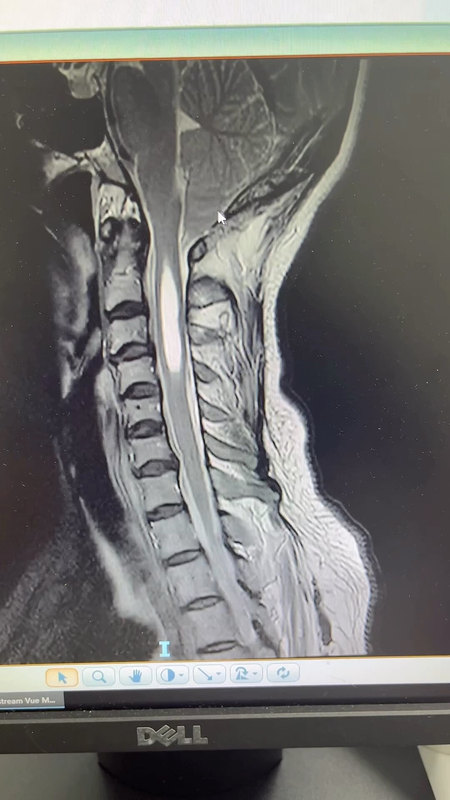

來源:丁香園 頸椎后路單開門椎管擴大成形術是治療多節(jié)段頸椎間盤突出癥、頸椎管狹窄癥及后縱韌帶骨化癥等頸椎疾病的常用術式。在單開門術中準備鉸鏈時,需保留內(nèi)層骨皮質(zhì),形成不全骨折的骨槽,以利椎板穩(wěn)定及鉸鏈側骨性愈合。椎板鉸鏈側的穩(wěn)定及其良好的骨性愈合是維持椎板開門狀態(tài)和神經(jīng)功能恢復的重要因素。但術后常發(fā)現(xiàn)椎板鉸鏈側出現(xiàn)完全骨折的現(xiàn)象,可能導致椎板不穩(wěn)定。不穩(wěn)定的椎板漂浮在椎管上,若向椎管內(nèi)移位塌陷則可能壓迫或刺傷脊髓、神經(jīng)根、造成嚴重的神經(jīng)并發(fā)癥。由此可見,鉸鏈側的骨性愈合對術后椎板的長期穩(wěn)定具有重要意義,只有鉸鏈側達到骨性愈合,才能避免椎板再關門的風險。近年來,頸椎微型鋼板逐漸被用于開門后鉸鏈側的固定,以減少或避免椎板再關門的發(fā)生。但單獨采用微型鋼板進行固定的長期臨床療效仍缺乏足夠的研究證據(jù)。為了進一步以評價單獨使用鋼板固定鉸鏈的頸椎單開門椎管擴大成形術的臨床療效,韓國學者Youn-Kwan Park等進行了一項回顧性臨床研究,持續(xù)觀察頸椎單開門椎管擴大成形術后鉸鏈側骨性愈合的狀態(tài)和時程,該研究結果已在近期的The Spine Journal雜志上發(fā)表。在該研究中,研究者將2005年2月至2011年1月期間79例在韓國高麗大學九老醫(yī)院接受頸椎單開門椎管擴大成形術的脊髓型頸椎病患者納入為研究對象。這些患者均采用鋼板進行頸椎單開門椎管擴大成形術的固定,共對125處鉸鏈進行了術后CT掃描,以評價鉸鏈骨折的骨性愈合狀態(tài)。通過對患者行頸椎CT掃描并測量影像學參數(shù),持續(xù)觀察鉸鏈側骨折隨著時間的變化。分別采用日本骨科協(xié)會(JOA)評分、頸椎功能障礙指數(shù)(NDI)、手臂疼痛的視覺模擬量表(VASa,0-10)評分,以及頸部疼痛的VAS(VASn,0-10)評分對患者術前以及術后隨訪第12個月時患者的功能狀態(tài)進行評價。圖1. 典型的早期鉸鏈骨折患者術后一周時的CT影像:變形良好的鉸鏈(上圖),部分斷裂的鉸鏈(中圖),已骨折的鉸鏈(下圖)。星號所示為鉸鏈內(nèi)側骨皮質(zhì)斷裂。圖2. 典型的鉸鏈骨性愈合患者術后第4個月時的CT影像:(A 與 B)一期愈合,(C 與D)二期愈合,(E)已骨折,(F)已骨折伴骨痂形成,(G) 移位伴骨痂形成,(H)未愈合的鉸鏈。圖3. 各時間點愈合結果較差鉸鏈的比例(上圖)。鉸鏈骨折的好發(fā)部位(下圖)。該研究結果顯示,絕大多數(shù)的鉸鏈起初均可以保持良好的彎曲。只有9%的患者術后第一周就已出現(xiàn)骨折或存在骨折的風險。在術后第4個月時,有62%的鉸鏈彎曲良好的患者實現(xiàn)了一期愈合且無骨痂形成。余下38%的患者被歸為“已骨折”或正處于“二期愈合”的過程中。至術后第1或2年時,除1處鉸鏈以外幾乎所有的鉸鏈骨折均愈合良好,實現(xiàn)了二期愈合。根據(jù)術后12個月的VASn評分與NDI評分結果,歸為“已骨折”或“二期愈合”的鉸鏈數(shù)量與術后軸向頸痛密切相關。圖4. 上圖: 累及C2或C7的患者術前與術后VASn評分差異的平均值;下圖:鉸鏈骨折的數(shù)量。圖5. 一例62歲男性脊髓型頸椎病患者術后隨訪的CT掃描結果。該研究結果表明,盡管單獨使用鋼板固定的頸椎單開門椎管擴大成形術是用于多節(jié)段頸椎解壓的一種安全和可靠術式,但其并不能為開門側提供足夠的穩(wěn)定性以實現(xiàn)一期愈合。因此,對采用此類術式的患者,需積極預防術后鉸鏈側的遲發(fā)型骨折并減少術后軸向頸痛。文獻原文: 頸椎單開門術后應預防遲發(fā)型鉸鏈骨折